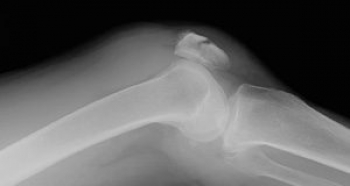

ɨ³¸¹ü¹üÀÞ¤ÎʬÎà

­¡²£¹üÀÞ

­¢½Ä¹üÀÞ

­£Ê´ºÕ¹üÀÞ

ɨ³¸¹ü¹üÀÞ¤ÎȯÀ¸µ¡½ø

ľã³°ÎÏ

žÅݤʤɤˤè¤êɨÁ°Êý¤ò¶¯ÂǤ·¡¢¹üÀÞ

²ðã³°ÎÏ

ÂçÂÜ»ÍÆ¬¶Ú¤Î¸£°ú¤Ë¤è¤ê¡¢¹üÀÞ

ɨ³¸¹ü¹üÀޤξɾõ

ɨ´ØÀá¤Î¼ðı¤ÈáÖÄˤ¬ÃøÌÀ

¹üÀÞÉô¤Î¸Â¶ÉÀ­°µÄË

ɨ³¸ç§Ëì¤ÎÃÇÎö¤ò¹çÊ»¤ò¤·¤Æ¤¤¤ë¤È¹üÀÞÉô¤ÎÎ¥³«¤ÈÈéÉæ¤Î´Ù±ú¤¬¿¨ÃΤ¹¤ë¡£

ľã³°ÎϤÏɨÁ°Ì̤ÎÈéÉæÂ»½ý

´°Á´¹üÀÞ¤Ïɨ´ØÀ῭ŸÎϤ˾㳲